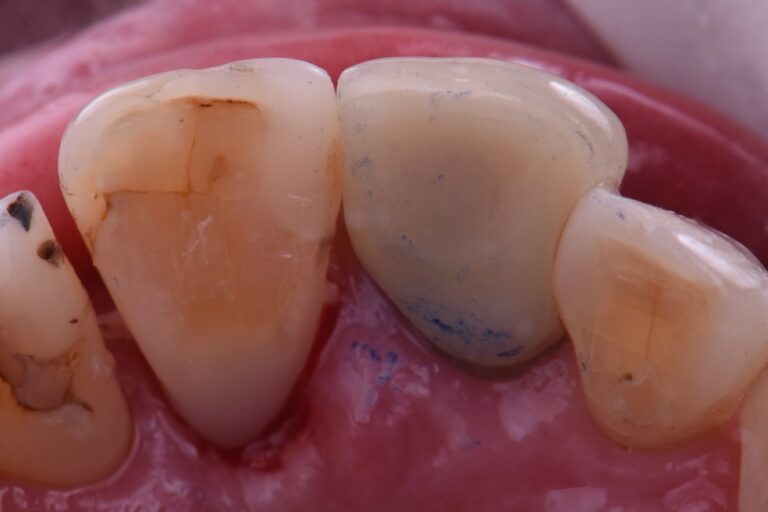

Occlusal Wear In Dentistry . Abstract dental wear is loss of tooth structure resulting from erosion, atrition, abrasion, and, possibly, abfraction. Dental or tooth wear is a physiological process in the life cycle of teeth. Learn how to diagnose and treat different types of tooth wear, including erosion, attrition, abrasion, and abfraction, with this infographic from usc's. The aim of this series of four articles on tooth wear management is to provide the reader with the necessary information in. Tooth wear facets are characterized as flat, round or sharply angled and polished surfaces on the occlusal or incisal areas of the teeth and may. Emphasises the need for an accurate diagnosis and the strategic management of occlusal changes to treat complex cases. Loss of the occlusal surface may cause excessive tooth wear. This article reviews the causes, diagnosis and treatment of severe tooth wear, a common challenge for restorative dentistry. The pms occlusal scheme, unlike the gnathologic concept, encouraged multiple occlusal contacts during lateral movements. It also discusses the effects of tooth.

Loss of the occlusal surface may cause excessive tooth wear. It also discusses the effects of tooth. The aim of this series of four articles on tooth wear management is to provide the reader with the necessary information in. The pms occlusal scheme, unlike the gnathologic concept, encouraged multiple occlusal contacts during lateral movements. Learn how to diagnose and treat different types of tooth wear, including erosion, attrition, abrasion, and abfraction, with this infographic from usc's. Dental or tooth wear is a physiological process in the life cycle of teeth. Emphasises the need for an accurate diagnosis and the strategic management of occlusal changes to treat complex cases. Tooth wear facets are characterized as flat, round or sharply angled and polished surfaces on the occlusal or incisal areas of the teeth and may. This article reviews the causes, diagnosis and treatment of severe tooth wear, a common challenge for restorative dentistry. Abstract dental wear is loss of tooth structure resulting from erosion, atrition, abrasion, and, possibly, abfraction.

Occlusal Wear In Dentistry This article reviews the causes, diagnosis and treatment of severe tooth wear, a common challenge for restorative dentistry. Dental or tooth wear is a physiological process in the life cycle of teeth. Tooth wear facets are characterized as flat, round or sharply angled and polished surfaces on the occlusal or incisal areas of the teeth and may. The pms occlusal scheme, unlike the gnathologic concept, encouraged multiple occlusal contacts during lateral movements. The aim of this series of four articles on tooth wear management is to provide the reader with the necessary information in. Emphasises the need for an accurate diagnosis and the strategic management of occlusal changes to treat complex cases. Abstract dental wear is loss of tooth structure resulting from erosion, atrition, abrasion, and, possibly, abfraction. Loss of the occlusal surface may cause excessive tooth wear. It also discusses the effects of tooth. Learn how to diagnose and treat different types of tooth wear, including erosion, attrition, abrasion, and abfraction, with this infographic from usc's. This article reviews the causes, diagnosis and treatment of severe tooth wear, a common challenge for restorative dentistry.